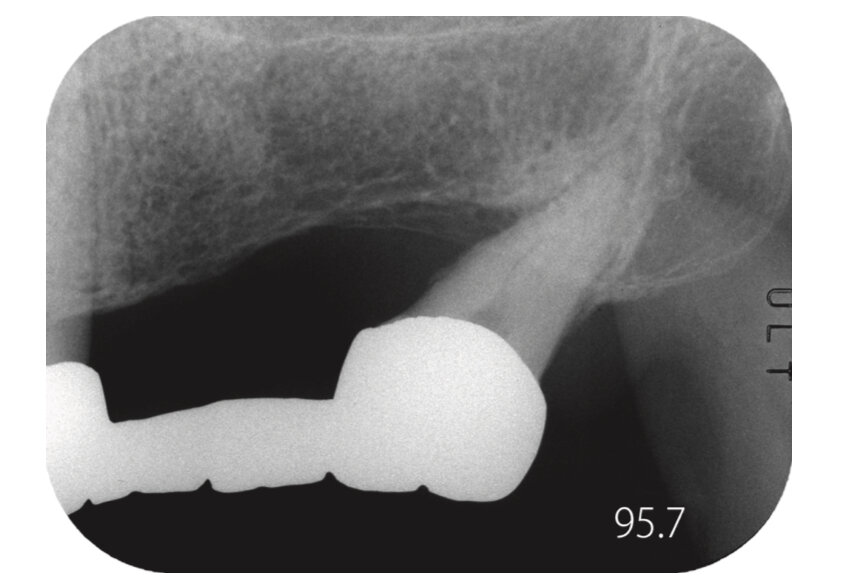

Рис. 1. Что мы можем определить по одной рентгенограмме? (Мужчина, 48 лет)

Посмотрите на рентгенограмму на рис. 1. Пациенту необходима замена старой конструкции протеза. Что вы думаете по этому поводу? Наверняка, первыми мыслями будут: «Какой тип протезирования выбрать?» или «Какие манипуляции необходимы перед протезированием?». В итоге, независимо от выбранного плана лечения, состояние тревожности не будет нас покидать. Почему же так происходит?

Вернемся к рис. 1. В этом случае 48-летний пациент, ссылаясь на занятость, отказался от предложенного ортодонтического выравнивания наклона зуба мудрости. В итоге было решено установить условно-съемный мостовидный протез. Двумя причинами выбора этой конструкции являлись: наклон опорного зуба мудрости и костный карман на мезиальной поверхности. Разумеется, выбор такой конструкции нежелателен при поражении пародонта, однако такую конструкцию при необходимости доктор может снять и провести чистку и лечение пародонта зуба мудрости.